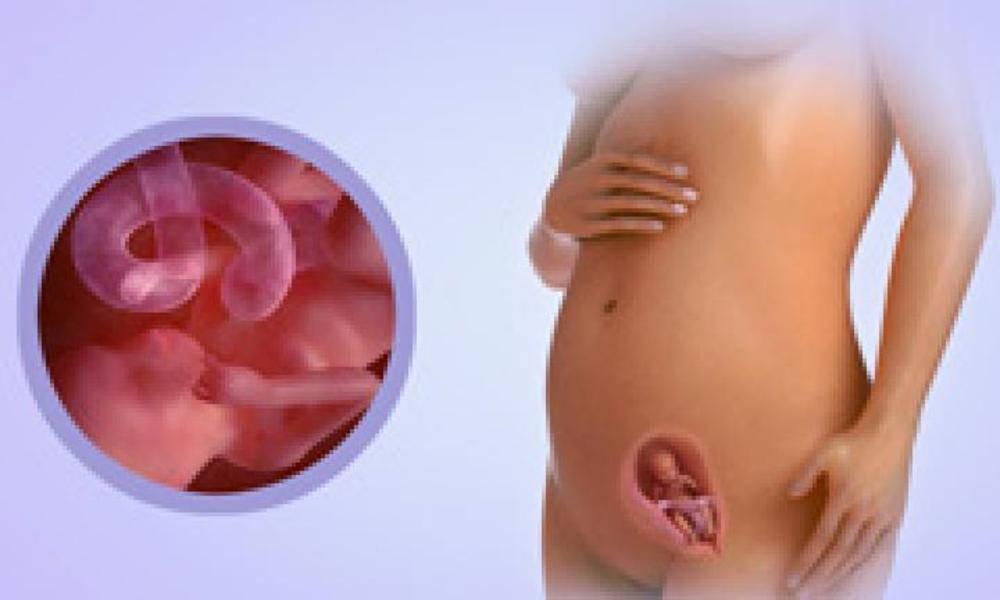

16-17 недель беременности: развитие малыша